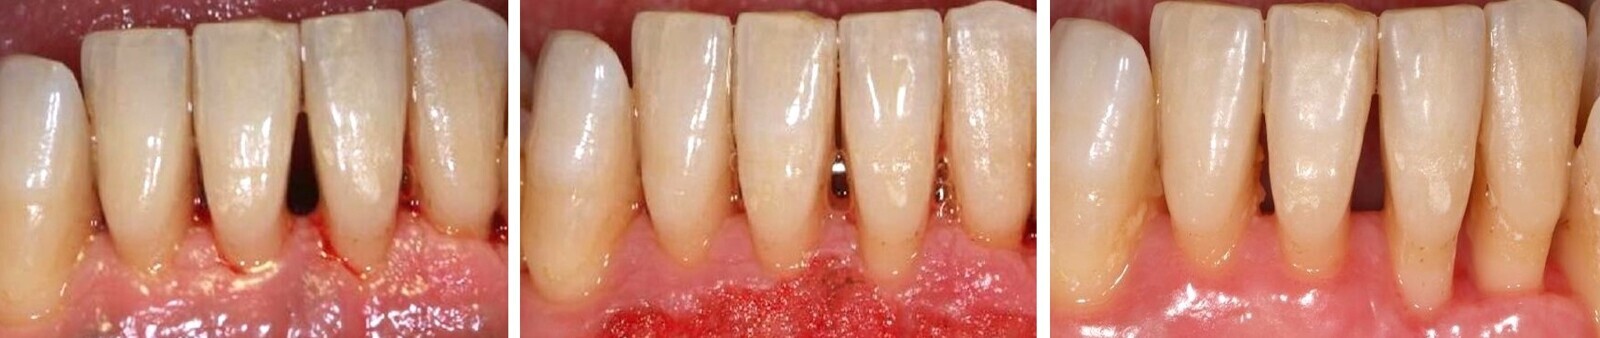

Este tratamiento se puede realizar mediante la técnica convencional (Figura 1), o con el láser de erbio, bien sea YAG o Er,Cr:YSGG (Waterlase) (Figura 2). Pero el uso del láser no elimina ni sustituye a las curetas, sino que las complementa, mejorando y potenciando el resultado del tratamiento (Figura 3).

Figura 1. El tratamiento de la enfermedad periodontal se puede realizar mediante la técnica convencional de raspado y alisado radicular.

Figura 2. El láser de erbio, bien sea YAG o Er,Cr:YSGG, es eficaz para el tratamiento de la enfermedad periodontal.

Figura 3. El uso del láser no sustituye a las curetas, sino que las complementa, mejorando y potenciando el resultado del tratamiento.

El raspado y alisado radicular fue descrito hace muchos años por la Academia Americana de Periodoncia como un tratamiento meticuloso, arduo y que lleva tiempo, pero que al mismo tiempo y según la evidencia, ha demostrado ser muy eficaz en el control de la enfermedad periodontal. Si bien debemos considerar este tratamiento convencional como “gold standard”, no es menos cierto que puede ser complementado, simplificado e incluso mejorado con el láser.

La combinación del raspado y alisado radicular con el láser produce una mejoría clínica moderada en comparación con la técnica convencional, como constataron Borrajo y colaboradores1.

En otro estudio, Castro y colaboradores fueron más allá y concluyeron que además de lo anterior, el láser de diodo puede ser utilizado rutinariamente como complemento al raspado y alisado radicular sin que dañe el cemento radicular2. Esto debe darnos tranquilidad en cuanto al uso de esta tecnología en este tratamiento concreto y llevarnos a utilizarlo en nuestro día a día, siguiendo, eso sí, los parámetros de seguridad adecuados.